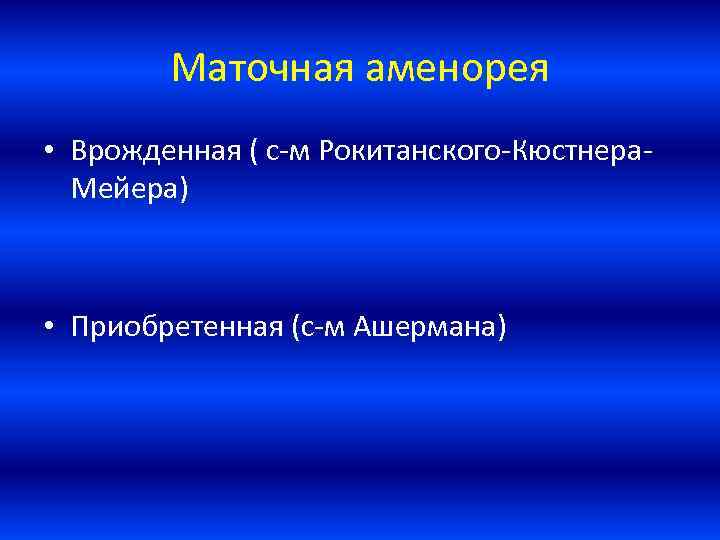

Медицинская визуализация: Признак Кюстнера-Чукалова